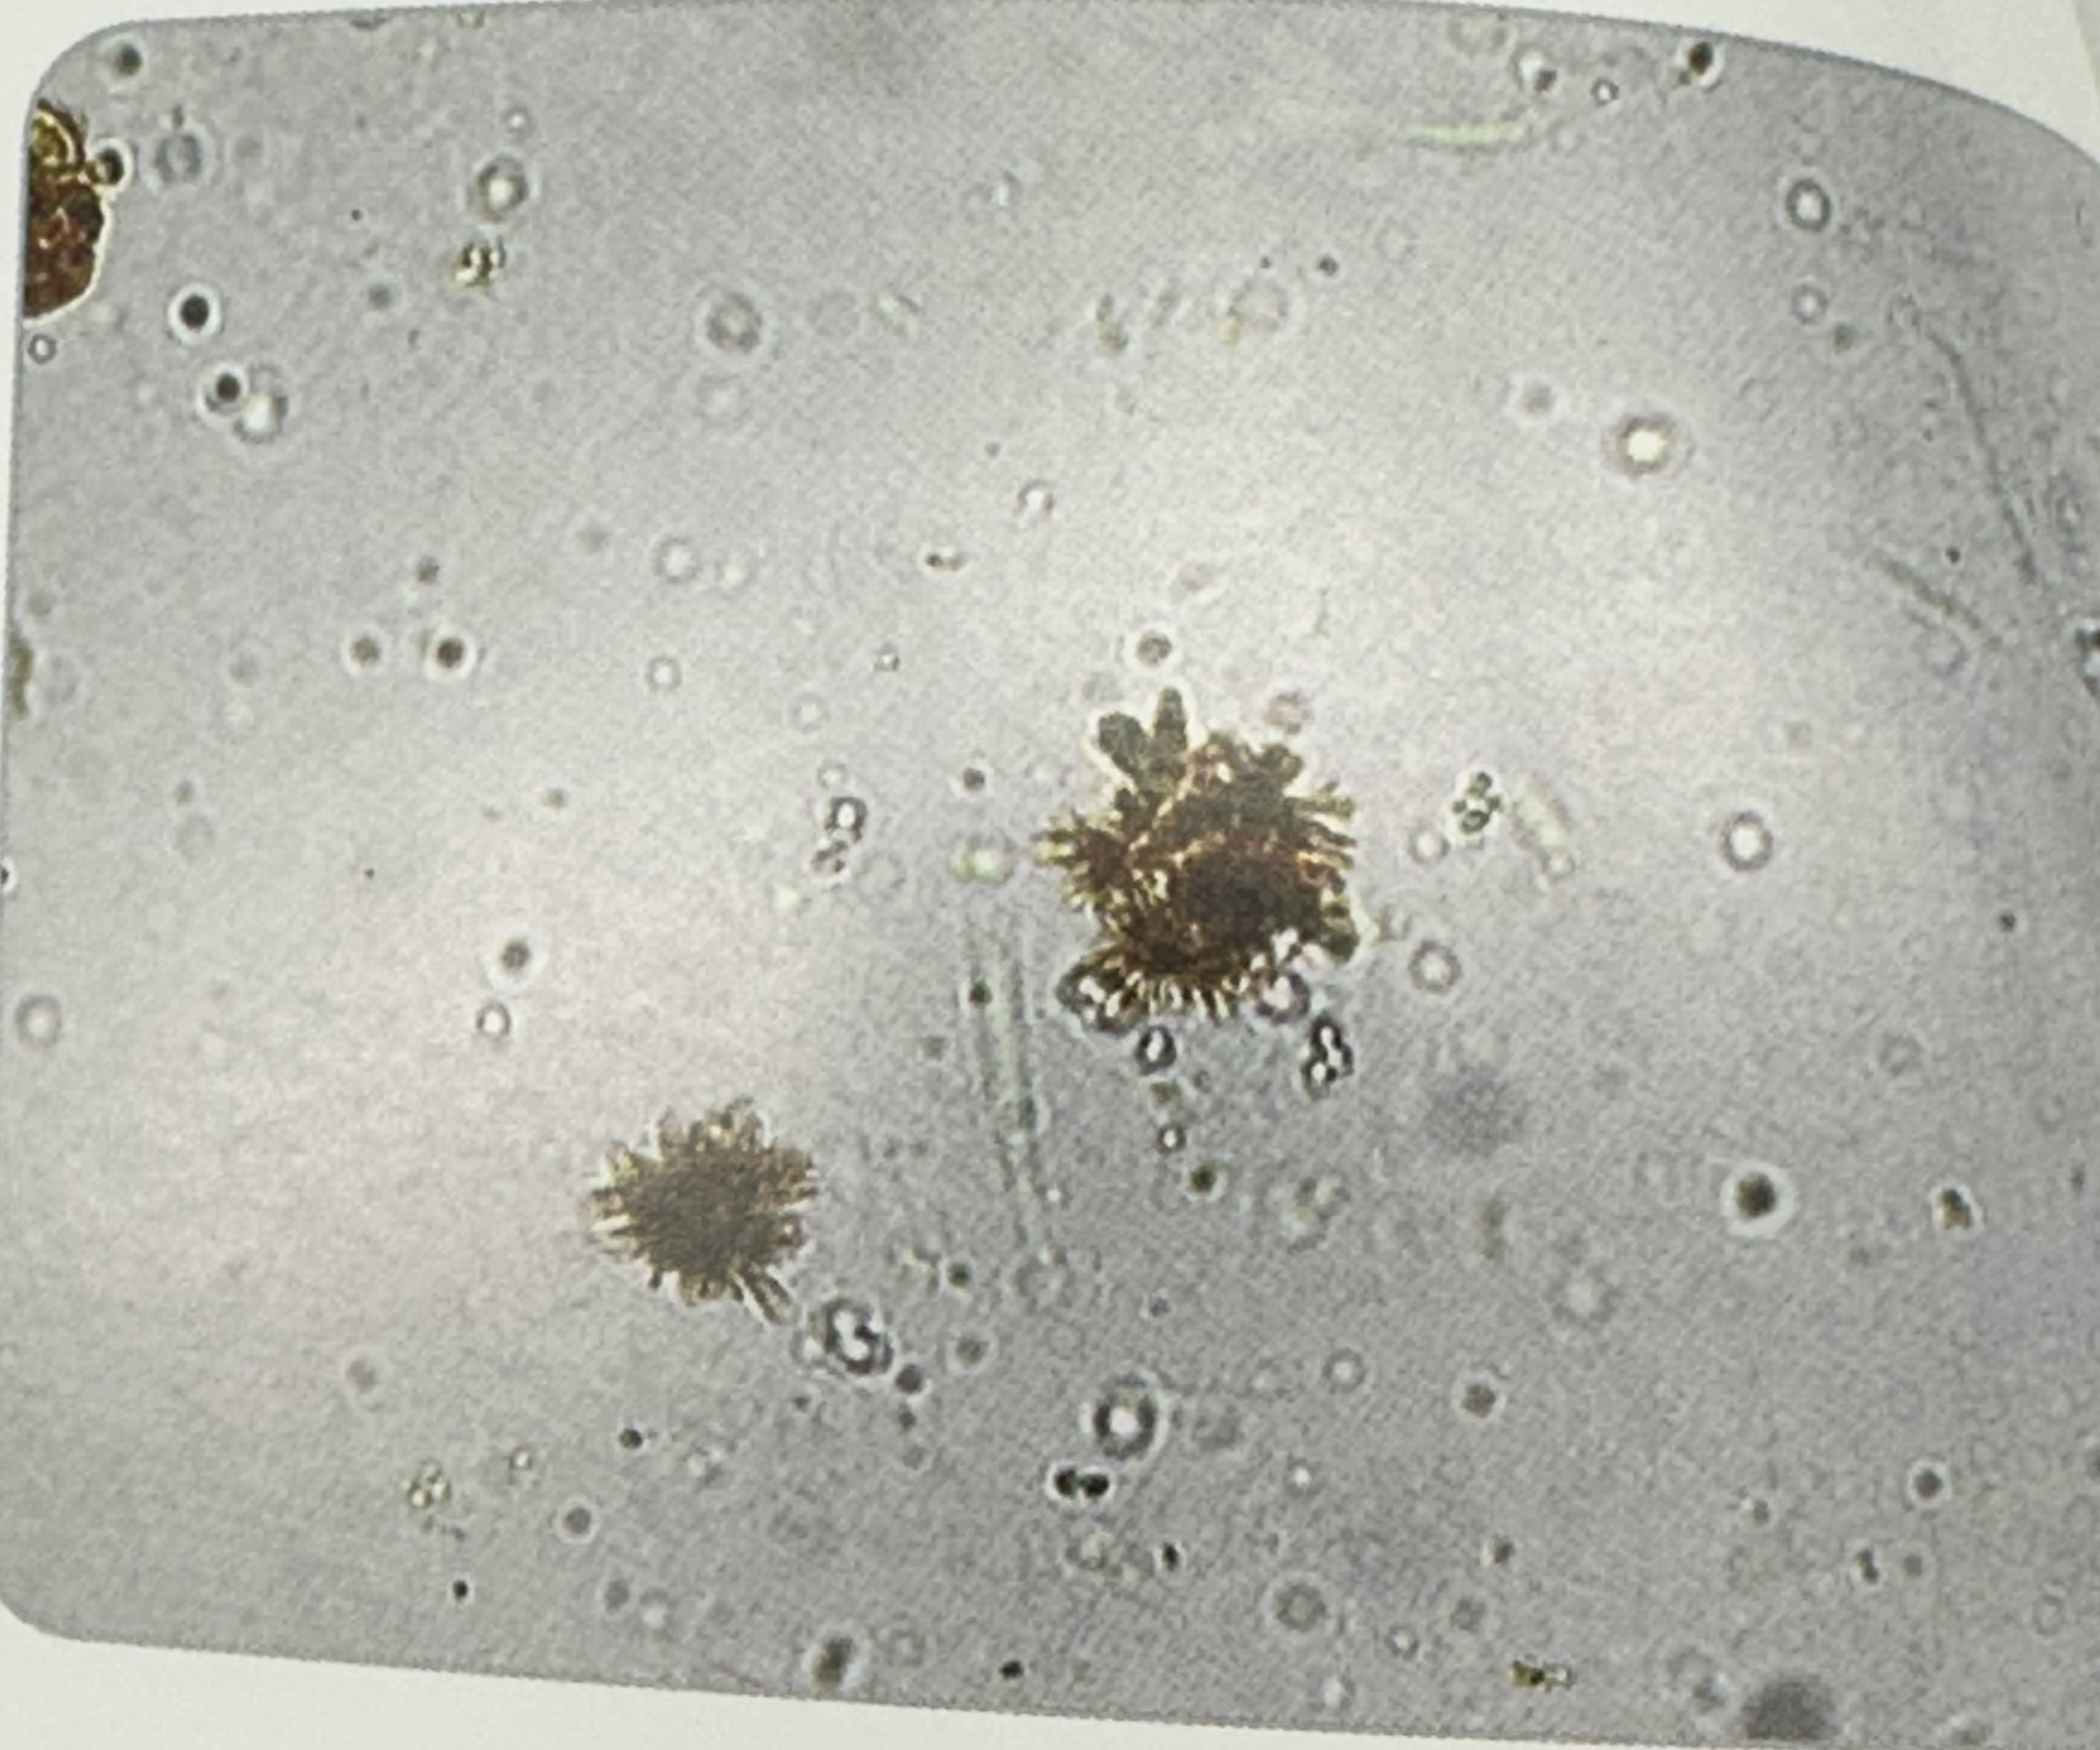

Ammonium Biurate

spheres with striations

Irregular thorny apple

Alkaline urine